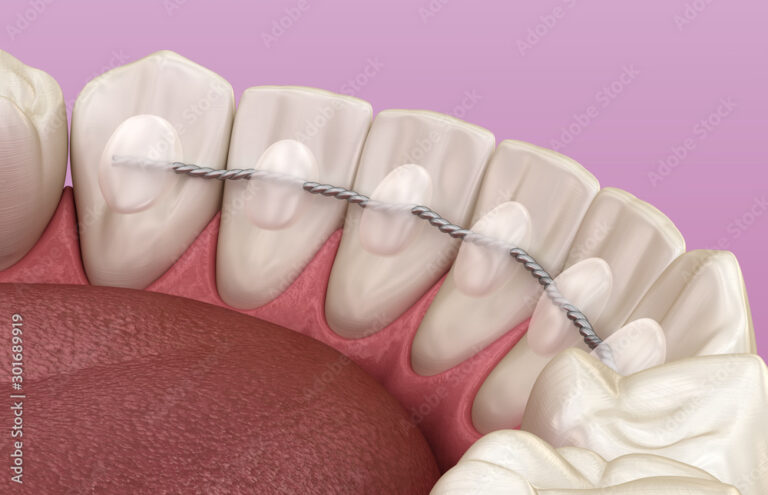

Der geklebte Retainer

Es handelt sich um einen dünnen Draht, der zur zusätzlichen Retention auf die Innenseite der Ober- bzw. Unterkieferfrontzähne geklebt wird. Er ist somit praktisch unsichtbar und kann einige Jahre im Mund belassen werden. Wenn sich eine Klebstelle lösen sollte, werden die Patient:innen angewiesen, sofort für eine Reparatur in die Ordination zu kommen.